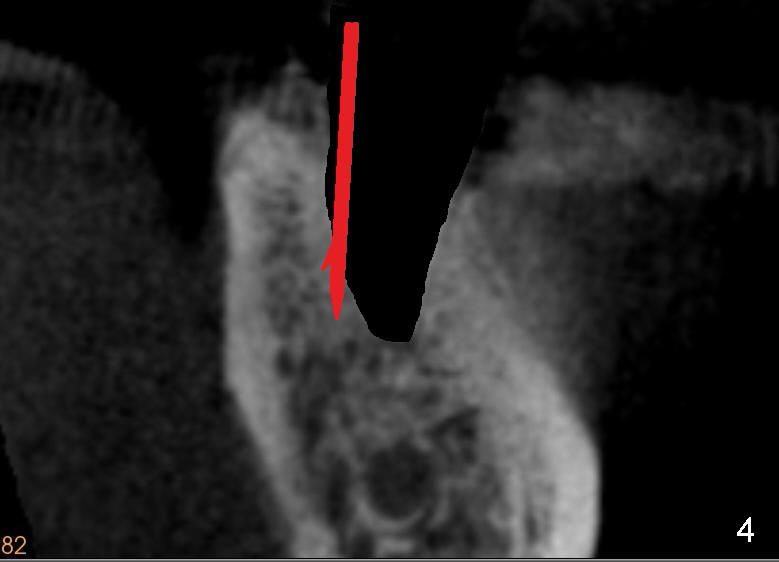

To overcome this problem, a pilot drill penetrates the buccal slope of the lingual wall (Fig.3 red line). Once the pilot drill gets "bite", change its direction to finish osteotomy (Fig.4). When subsequent drills are being used, lean each drill lingually, against "natural" tendency of the drill sliding buccally.